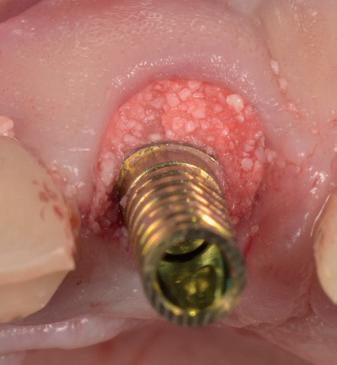

Na de genezingsperiode werd eerst een OPT röntgenopname vervaardigd om de genezing van de implantaten, kaakverbreding en sinusbodemelevatie te beoordelen. Er waren geen complicaties opgetreden. Bij de tweede fase chirurgie is het van absoluut belang dat er minimaal 2-3 mm gekeratiniseerd weefsel aan de buccale zijde van de implantaten wordt verkregen, anders kan de patiënt de implantaten niet goed reinigen en door de trekkrachten van de mucosa ontstaat al gauw peri-implantaire ontstekingen en recessies. De incisie hoeft niet van tuber tot tuber te zijn, maar 2 incisies van de 16 tot de 12 en 26 tot de 22 is voldoende, waarbij de incisie genoeg gekeratiniseerd weefsel aan de buccale zijde bevat, dat naar

de buccale zijde van de implantaten wordt geduwd. Er werden 6 healing abutments van 6 mm hoogte op de implantaten geplaatst, waarna de wonden werden gehecht met een 6-0 monofilament hechtdraad. In de prothese werd een nieuwe softliner over de healing abutments geplaatst. Het weefsel dient minimaal 4 weken genezingstijd te hebben (afbeelding 6).